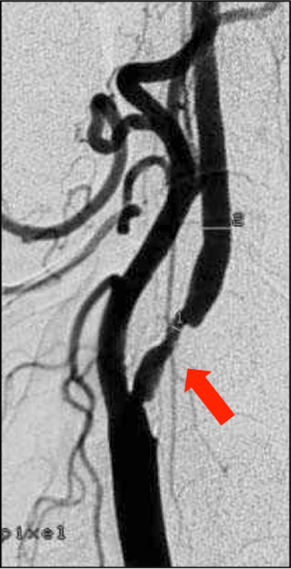

L’athérosclérose est une maladie des artères de moyen et gros diamètre, comme les artères carotides ou vertébrales qui cheminent dans le cou et les artères intracrâniennes qui cheminent à la base et autour du cerveau. Cette maladie est favorisée par le vieillissement et les facteurs de risque artériel comme l’excès de cholestérol, le tabac, le diabète et l’hypertension artérielle. La conséquence est la formation d’une plaque d’athérosclérose dans la paroi de l’artère, qui rétrécit la lumière de l’artère (Fig. 1). La plaque est composée d’un cœur lipidique et d’une chape fibromusculaire qui isole le cœur lipidique de la lumière artérielle. La gravité de cette maladie est liée à la survenue d’une thrombose (caillot sanguin) au contact d’une plaque devenue instable (Fig. 2). Le thrombus peut se développer dans la lumière artérielle, aboutir à l’occlusion complète de l’artère ou se fragmenter et occlure une artère distale de plus petit calibre. C’est ce qu’on appelle une embolie.

Fig.1 : Rétrécissement de l’origine de l’artère carotide interne par une plaque d’athérosclérose (flèche)